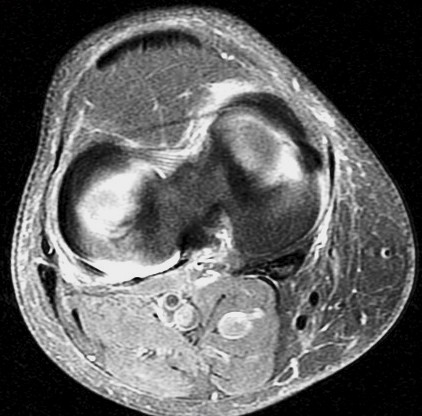

Figure 3 for case Unstable flap tear medial meniscus

Figure 3

With a displaced flap into the coronary recess. No sign of patellar dislocation. PD fat sat shows the inflammatory change that often accompanies and unstable tear. Displacement of meniscal tissue=instability.

Unstable flap tear medial meniscus